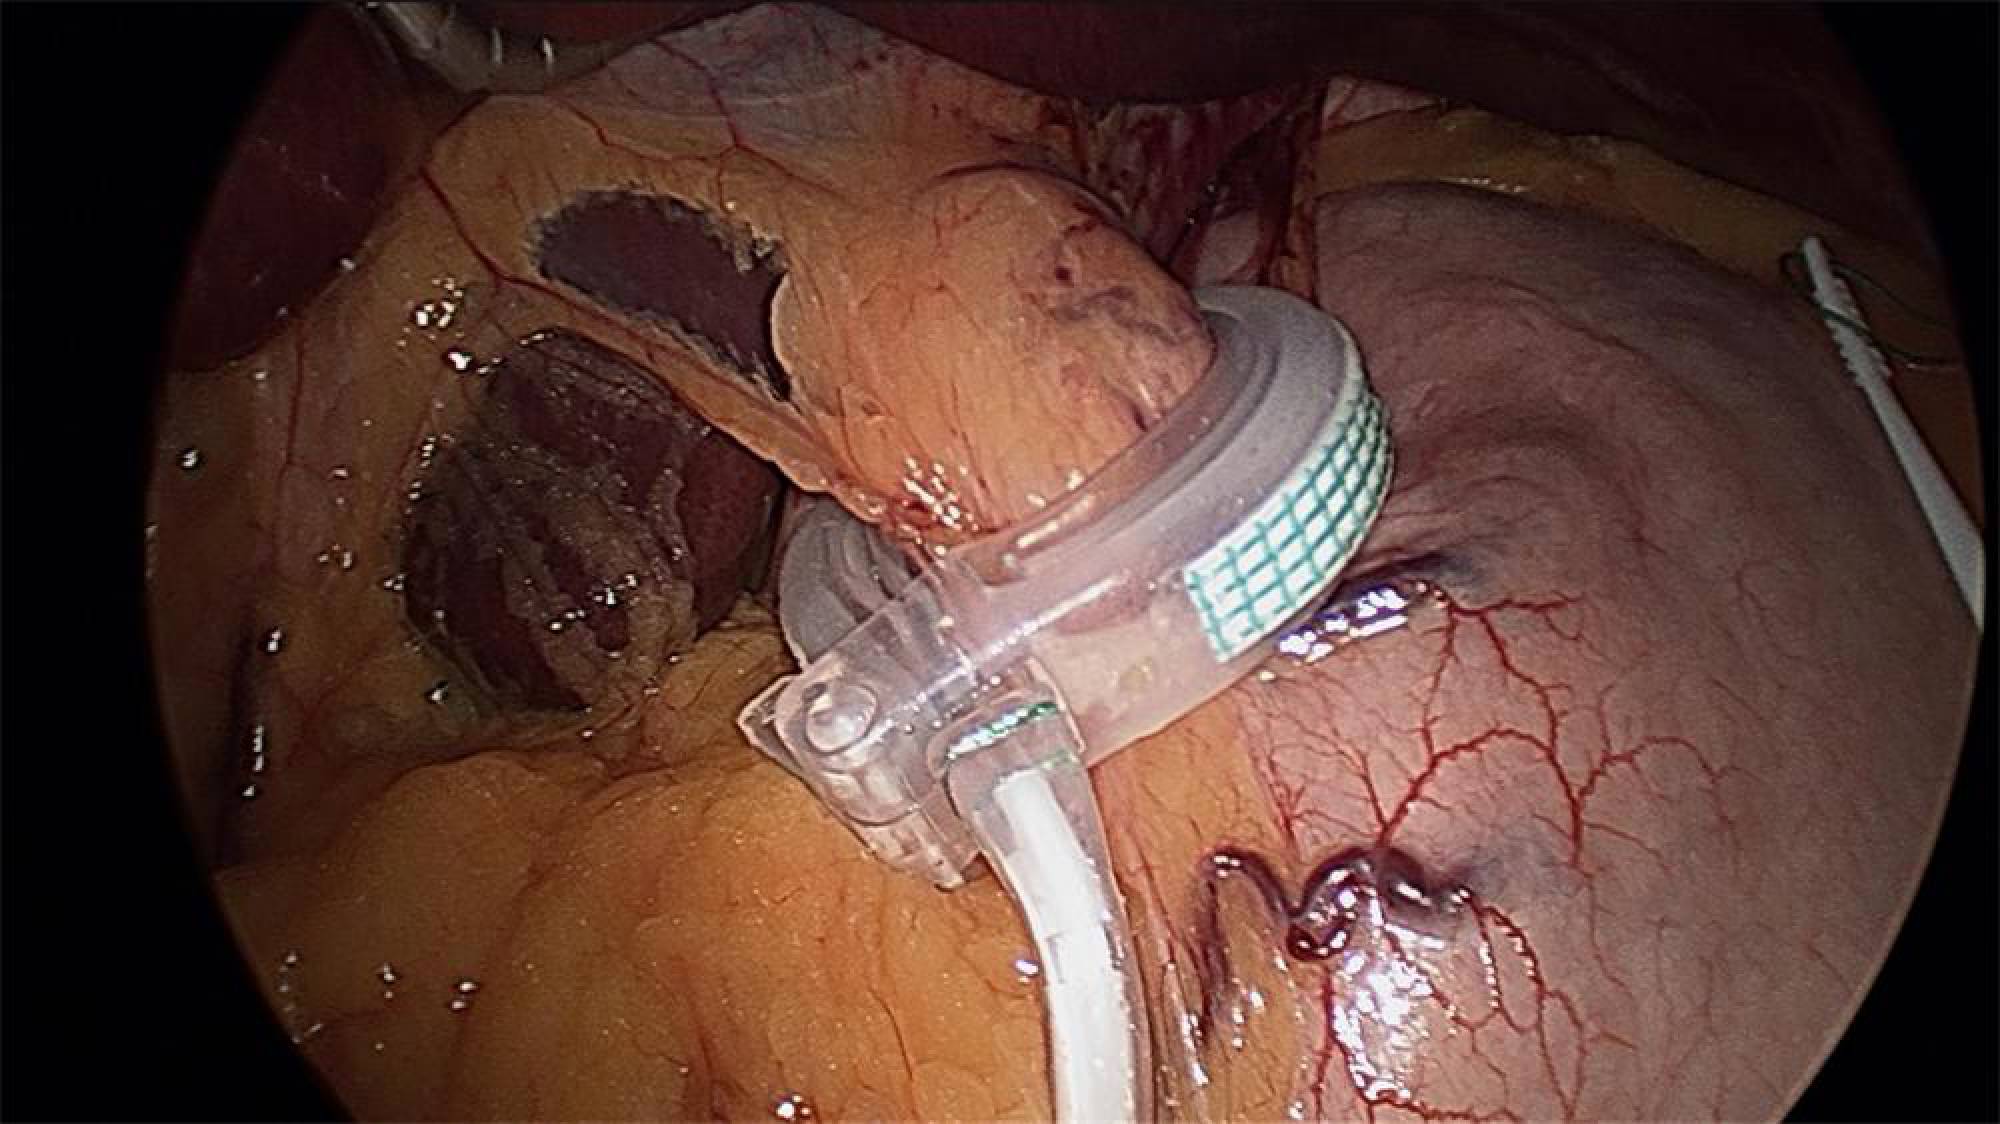

Inelul gastric ajustabil (gastric banding) este o tehnică restrictivă dezvoltată la începutul anilor 90 și constă în aplicarea laparoscopică a unui inel siliconic de volum variabil, ajustabil în parte superioară a stomacului.

Stomacul capătă aspectul de clepsidră cu o porțiune superioară de aproximativ 15 ml care comunică cu porțiunea inferioară printr-un tunel cu calibru ajustabil în funcție de ritmul de scădere ponderală prin intermediul inelului.

Are avantajul că nu secționează tubul digestiv și nu implică rezecții de segmente digestive, este reversibilă prin extragerea inelului însă are dezavantajul senzației de obstrucție postalimentară imediată, scăderea ponderală redusă față de alte tehnici (50% din excesul ponderal) și riscul reacției de respingere sau de eroziune locala.